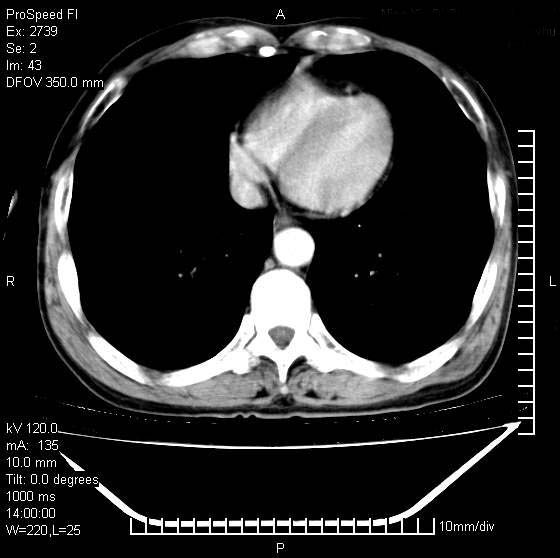

以下是引用andymaomao在2007-12-7 15:54:00的发言:[br]1.双上肺陈旧肺tb灶;[br]2.双中上肺矽肺;[br]3.双肺气肿;[br]4.图中箭头所指乃下腔静脉。

以下是引用山之魂海之韵在2007-12-7 18:59:00的发言:[br]支持矽肺,左肺上叶陈旧性结核,肺气肿。箭头所指乃下腔静脉。下腔静脉显影比主动脉显影迟,增强动脉后迟可以是不均匀的。

以下是引用chengjiaqiu1在2007-12-7 17:49:00的发言:[br]矽肺,左肺上叶陈旧性结核,肺气肿。中箭头所指乃下腔静脉。